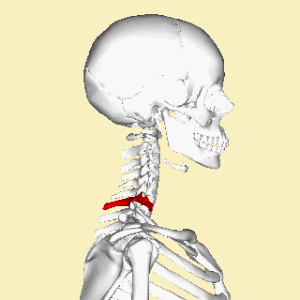

.jpg)

Position of cervical vertebrae (shown in red). Animation.